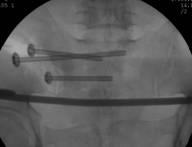

整个手术1小时内完成,通过术后CT影像证实3D打印导航模板引导骶髂螺钉置入安全、准确、创伤较小,手术时间短,患者也很快得到了较好的恢复。

术中C臂